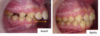

Bastien.

Bastien, 11 ans

Décalage squelettique des mâchoires, mâchoire du bas en retrait, dents du haut en avant, recouvrement excessif

Traitement sans extractions : appareil multi-attaches et surélévation antérieure fixée

Correction :

- du décalage osseux entre les mâchoires

- de l’avancée des incisives supérieures,

- de la supraclusion

Normalisation fonctionnelle

Amélioration de l’esthétique du profil

Durée : 23 mois de traitement (dont 5 mois avec la surélévation)

vue de profil avant et après traitement appareil multi-attaches